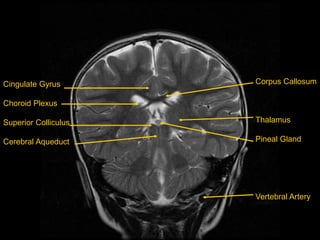

Coronal T2 Images

Cingulate Gyrus

Choroid Plexus

Superior Colliculus

Cerebral Aqueduct

Corpus Callosum

Thalamus

Pineal Gland

Vertebral Artery